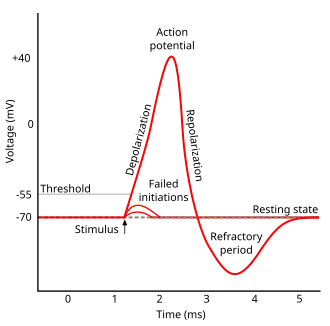

The different distribution of charges between the interior and the exterior of plasma membrane produce membrane potential (also transmembrane potential or membrane voltage). Two forces that establish and maintain resting membrane potential are passive (diffusion via channels) and active (sodium-potassium pump)[2]. With respect to the cytoplasmic side of neuron's membrane, typical values of the resting potential range from –70 to –80 millivolts. Like muscles, neurons use changes in their membrane potential as communication signals to receive, integrate, and send information. The difference in membrane potential can be produced by the permeability of the ions and the ion concentration on the two sides of the membrane. The opening and closing of ion channels can evoke a departure from the resting potential. This is called a hyperpolarization if the interior voltage becomes more negative (say from –70 mV to –80 mV) or depolarization if the interior voltage becomes less negative (say from –70 mV to –60 mV). In excitable cells, a clearly large depolarization can cause an action potential (long distance signals). But, the ion concentrations do not normally change very quickly. Therefore, graded potentials result from the passive electrical property of the neuronal membrane.

Action Potential

There are cell-to-cell communication with excitable membranes. They do not decrease in strength with distance and are referred to as "nerve impulse" or "spikes". The temporal sequence of action potentials generated by a neuron is called its "spike train". Stimulus changes permeability of neuron's membrane by opening specific voltage-regulated gated channels located on axons. Axons only could generate action potentials.

Generation of Action Potential (induced by depolarization) follows three sequential changes:

1.Sodium permeability increases and the membrane potential is on the contrary.

2.Sodium permeability decreases.

3.Potassium permeability increases and repolarization happens.